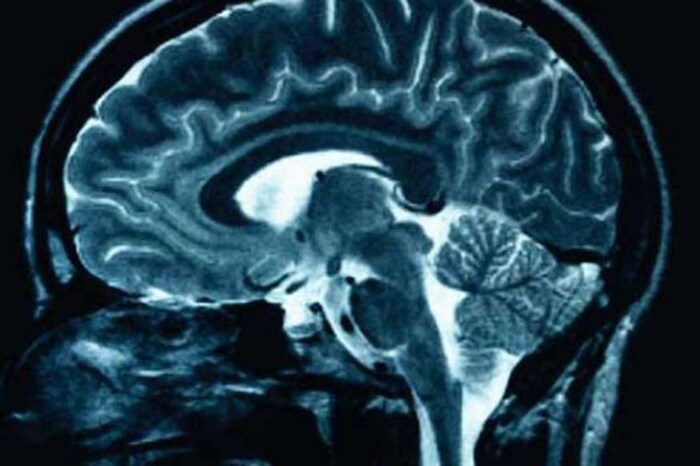

सर्वसामान्यांमध्ये मेंदूबद्दल नेहमीच चुकीचे समज असतात. त्यातही सांगायचं झालं तर बहुतेक लोकांना आजही असं वाटतं की, मेंदूचा 10 टक्के भागच काम करतो. PET आणि fMRI स्कॅन टेस्टच्या मार्फत आज आपण मेंदूबद्दल आतापर्यंत कोणत्या गोष्टी माहिती नव्हत्या ते जाणून घेऊ.